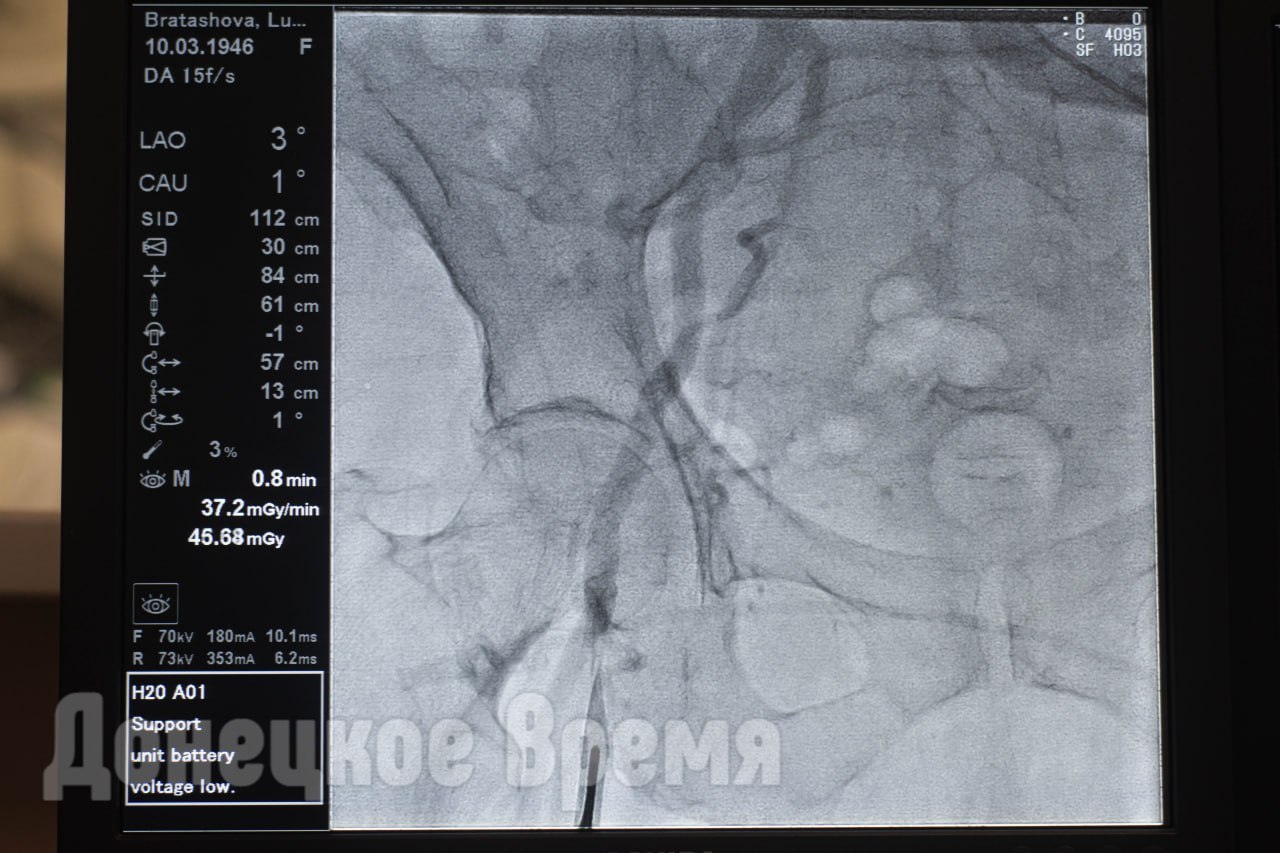

Без ножа и остановки сердца: в Донецке осваивают уникальные операции по замене аортального клапана

В отделении рентгенэндоваскулярной хирургии ИНВХ имени Гусака провели две операции по замене аортального клапана — без единого разреза, без остановки сердца. Вместо полостной хирургии — прокол в бедренной артерии. Вместо трех часов под наркозом — около часа. Вместо долгой реабилитации — три дня, и пациент дома.

Трансфеморальная имплантация аортального клапана — технология, которая пришла на смену тяжелой кардиохирургии. В России она появилась не вчера: в стране уже выполняют больше четырех тысяч таких операций в год, а планируют выйти на шесть тысяч. Для Донбасса же каждая такая операция — шаг к тому, чтобы высокотехнологичная помощь стала здесь доступной без выезда в другие регионы.